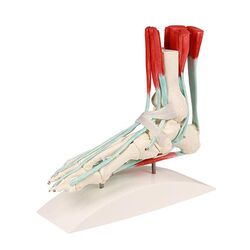

Pėdos skeletas su blauzdikaulio ir šeivikaulio įtvirtinimu, lankstus – Erler Zimmer

Pėdos skeletas su raiščiais – Erler Zimmer